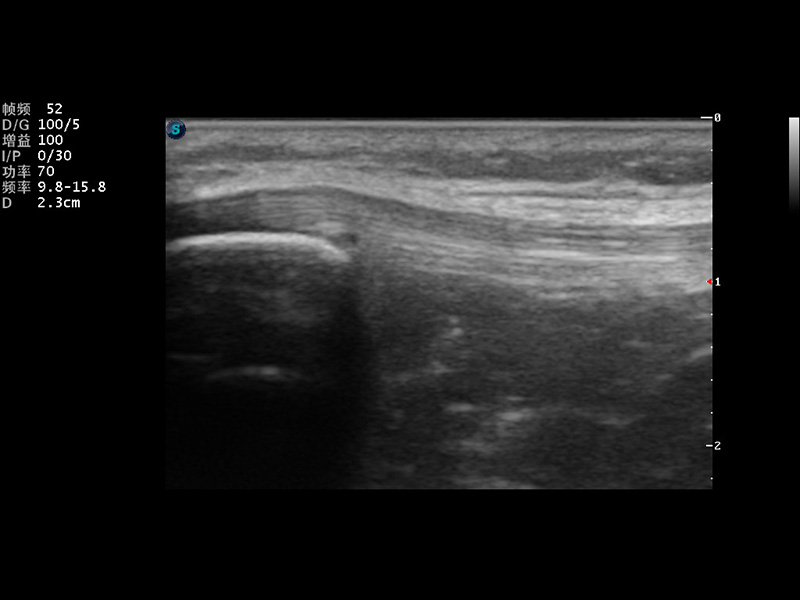

S9便携式彩色多普勒超声诊断仪是诸侯快讯官网研发的高端便携彩超设备,外观设计新颖、产品性能卓越。S9在便携超声领域采用了突破传统的触摸屏交互设计,并以先进的软件硬件技术和设计理念,为您带来清晰的图像质量、稳定的工作性能和便捷的操作体验。

μ-Scan微米成像